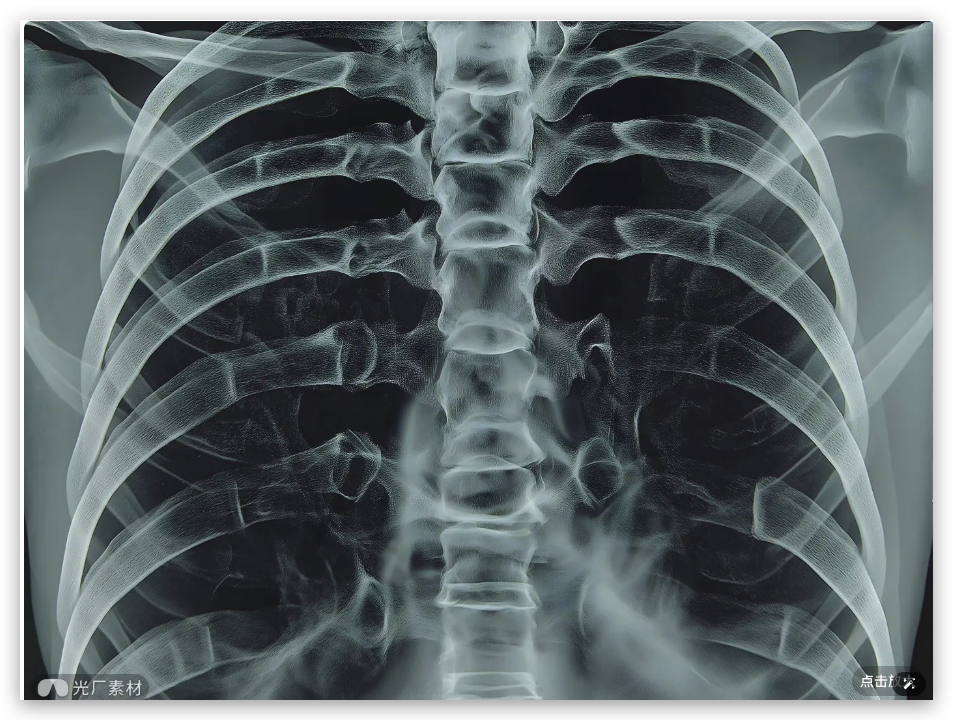

医疗影像分析

VLM 视觉模型另外一个使用场景就是在对医疗影像进行分析,比如:

提示词:这是一张胸部 X 光片,请检查一下肺部是否有异常结节。如果发现可疑区域,请圈出来,并大致测量一下它的最大径。另外,这张片子有点歪,请帮我把它旋转扶正,让脊柱保持垂直,看下效果。

Doubao-Seed-1.6-vision 就会依次自主调用工具,先是调用 rotate 进行旋转,

然后调用 zoom 工具进行局部多次放大:

视频如下: